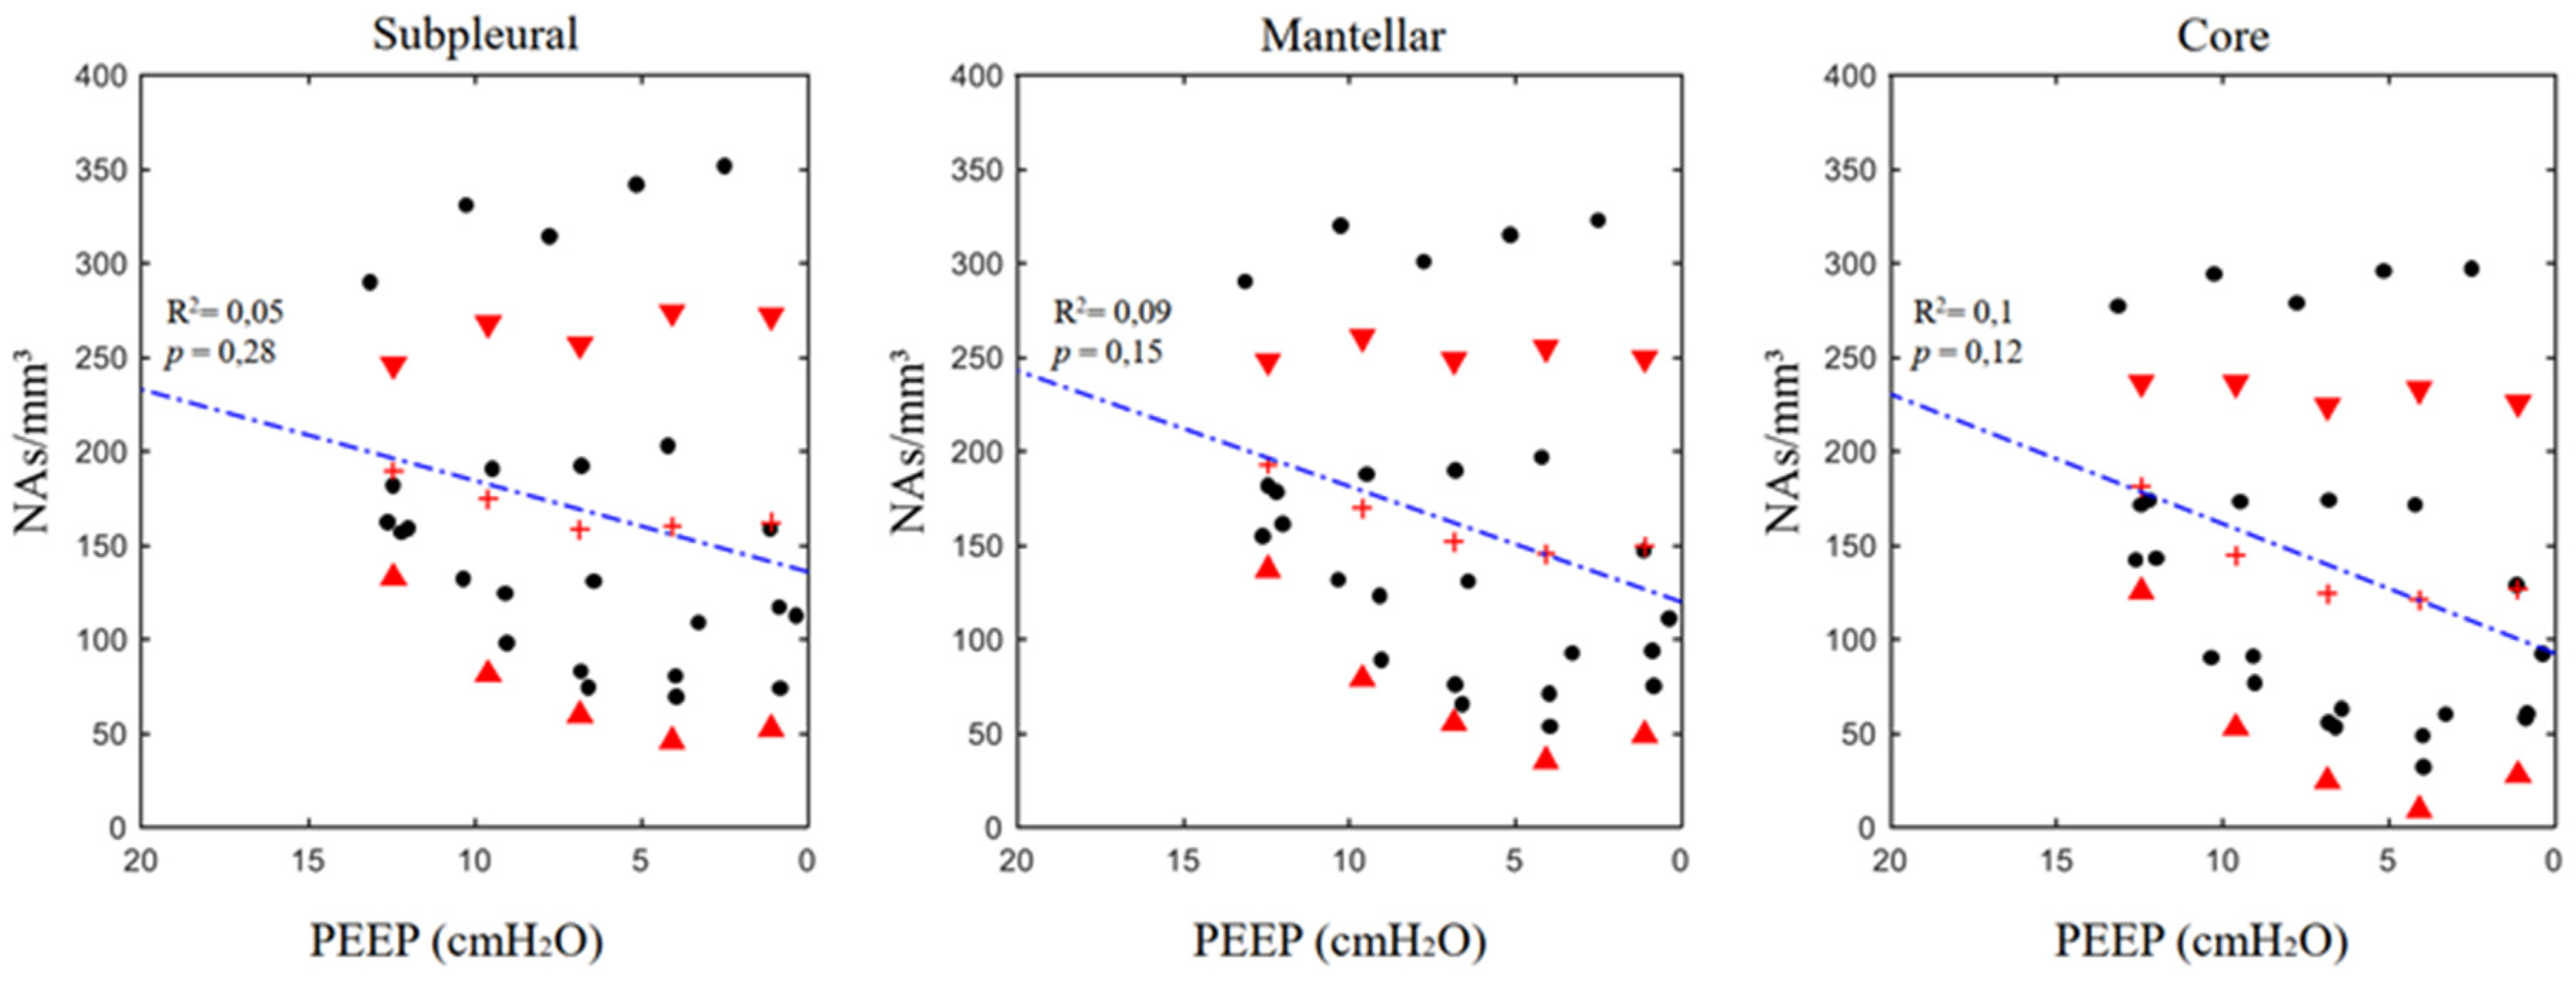

3.2. Airspaces Number and Dimension in the Three ROIs

| ROI | PEEP 12 | PEEP 9 | PEEP 6 | PEEP 3 | PEEP 0 | m | k | R2 | p | ||

| ASnum (n/mm3) | SUB | 189.7 ± 56.7 | 174.9 ± 93.3 | 158.7 ± 98.6 | 160.4 ± 114.1 | 162.5 ± 109.8 | 4.85 | 136.21 | 0.05 | 0.28 | |

| MAN | 193.0 ± 55.5 | 167.0 ± 90.9 | 152.3 ± 96.6 | 145.6 ± 109.7 | 149.7 ± 100.2 | 6.15 | 120.16 | 0.09 | 0.15 | ||

| COR | 181.2 ± 55.5 | 144.7 ± 91.7 | 124.6 ± 99.8 | 121.3 ± 111.7 | 127.1 ± 99.1 | 6.89 | 92.86 | 0.10 | 0.12 | ||